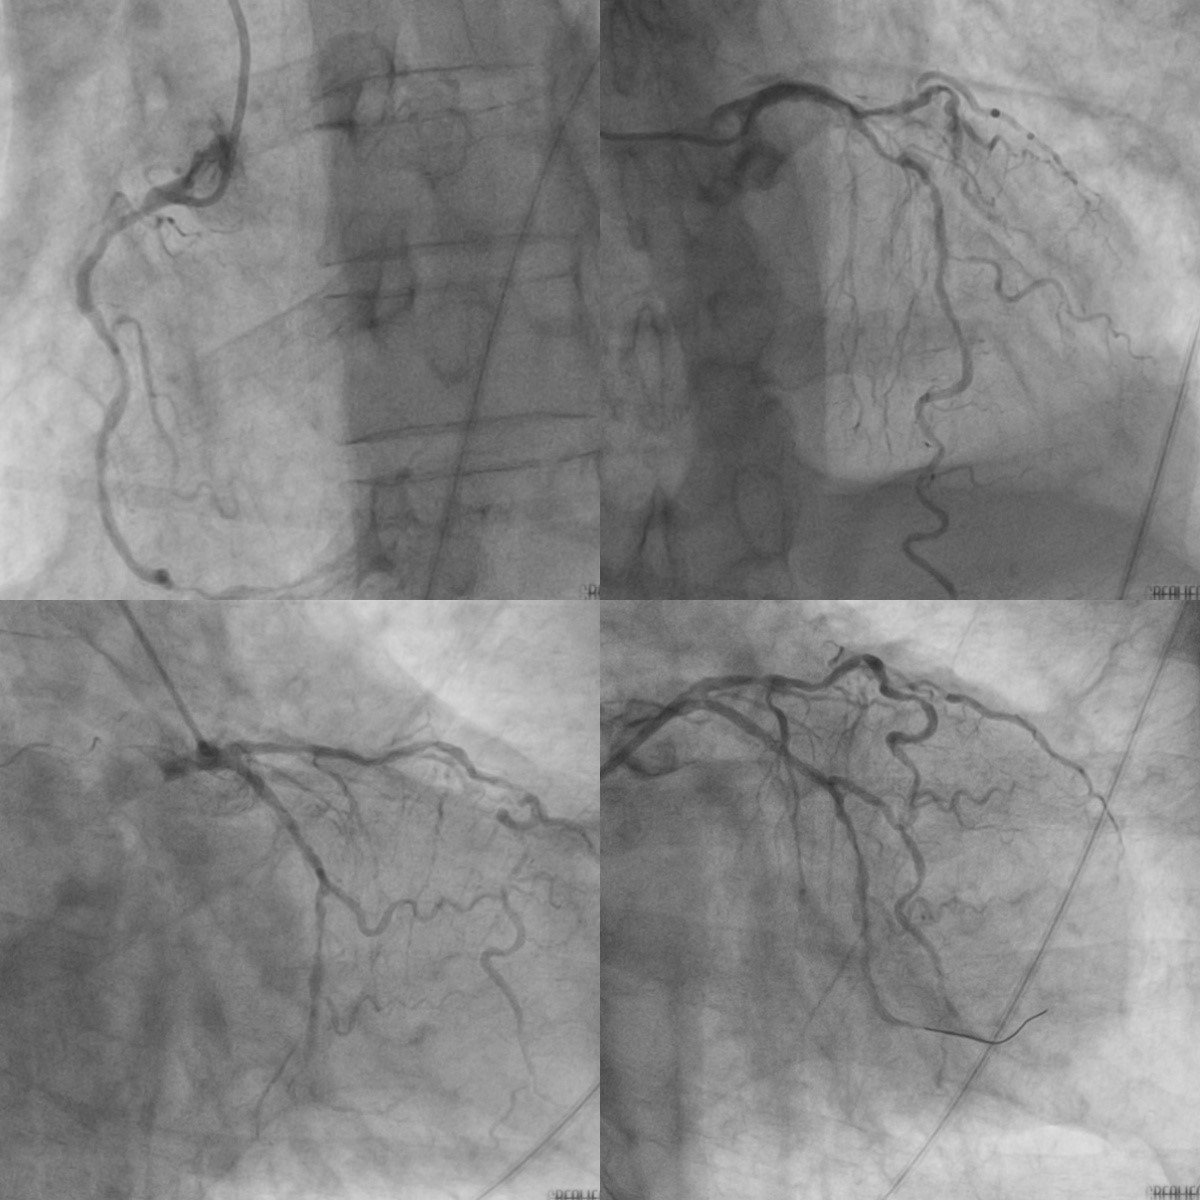

心内科会诊后紧急启动导管室,为患者行急诊PCI,术中提示患者三支病变,回旋支远段血管次全闭塞,考虑回旋支罪犯血管,迅速为患者行血运重建再灌注,主动脉球囊反搏(IABP)治疗。

冠脉造影